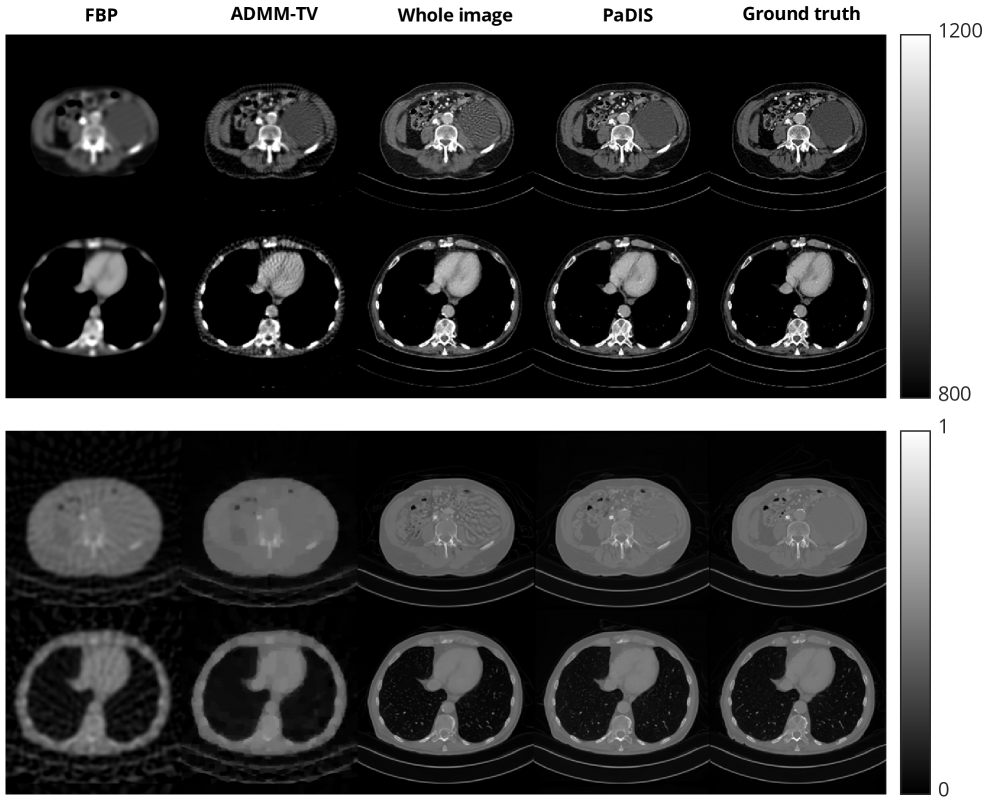

Refer to caption

Figure 5: Results of CT reconstruction. 60 views are used for the top two rows, 20 views are used for the bottom two rows. To better show contrast between organs, we use modified Hounsfield units (HU) in the top figure, while we use the same scale the images were trained on in the bottom figure.

In the bottom of Figure 5, some artifacts are present in the reconstructions obtained by the diffusion model methods, although they are more apparent in the whole image model than with PaDIS. The measurements are very compressed in this case, so it is very difficult for any model to obtain diagnostic-quality reconstructions; the baselines perform significantly worse in terms of quantitative metrics and exhibit severe blurring. In clinical settings, patient diagnosis are typically performed with CT scans consisting of hundreds of views. The top of Figure 5 shows that when 60 views are used, our proposed method yields a much better reconstruction without artifacts. Nevertheless, we show the potential of our proposed methods to reconstruct images from very sparse views with a decent image quality, which could be potentially used for applications such as patient positioning.